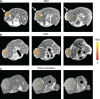

Angiogenesis is essential for tumor growth and metastatic potential and for that reason considered an important target for tumor treatment. Noninvasive imaging technologies, capable of visualizing tumor angiogenesis and evaluating the efficacy of angiostatic therapies, are therefore becoming increasingly important. Among the various imaging modalities, magnetic resonance imaging (MRI) is characterized by a superb spatial resolution and anatomical soft-tissue contrast. Revolutionary advances in contrast agent chemistry have delivered versatile angiogenesis-specific molecular MRI contrast agents. In this paper, we review recent advances in the preclinical application of paramagnetic and fluorescent liposomes for noninvasive visualization of the molecular processes involved in tumor angiogenesis. This liposomal contrast agent platform can be prepared with a high payload of contrast generating material, thereby facilitating its detection, and is equipped with one or more types of targeting ligands for binding to specific molecules expressed at the angiogenic site. Multimodal liposomes endowed with contrast material for complementary imaging technologies, e.g., MRI and optical, can be exploited to gain important preclinical insights into the mechanisms of binding and accumulation at angiogenic vascular endothelium and to corroborate the in vivo findings. Interestingly, liposomes can be designed to contain angiostatic therapeutics, allowing for image-supervised drug delivery and subsequent monitoring of therapeutic efficacy.